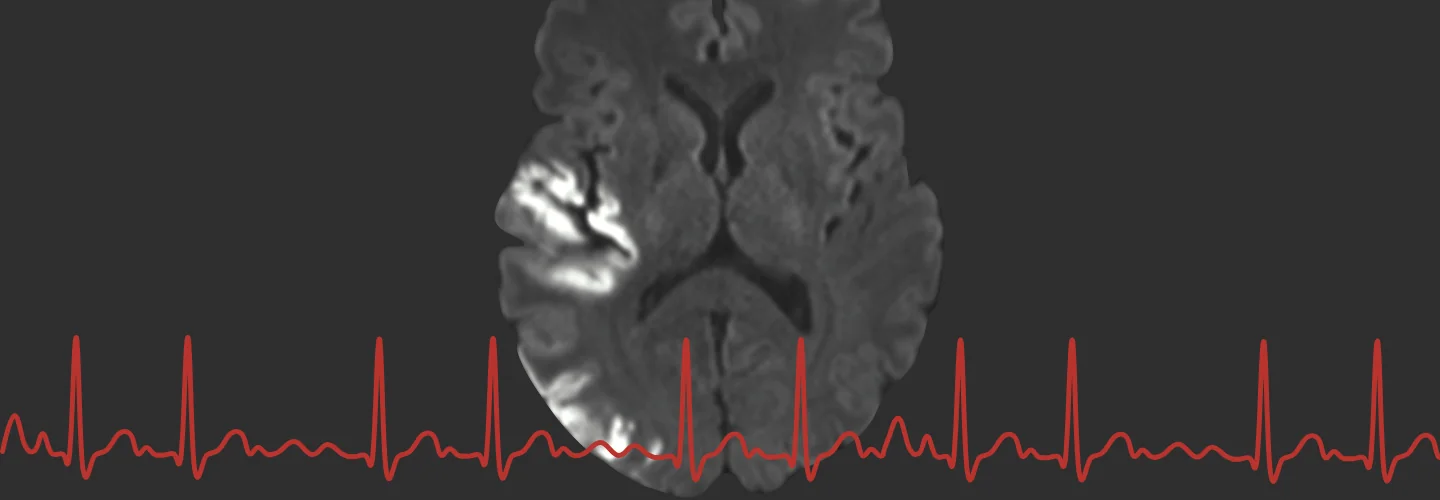

Our group - founded in 2018 with support from the Corona foundation – aims to study the crosstalk between brain and heart in patients with stroke.

We are an integrative research team located at the Center for Stroke Research Berlin and the Department of Neurology with Exp. Neurology at the Charité Universitätsmedizin Berlin, Germany.

We perform highly interdisciplinary research at the interface of neurology and cardiology, clinical epidemiology and cardiovascular imaging.